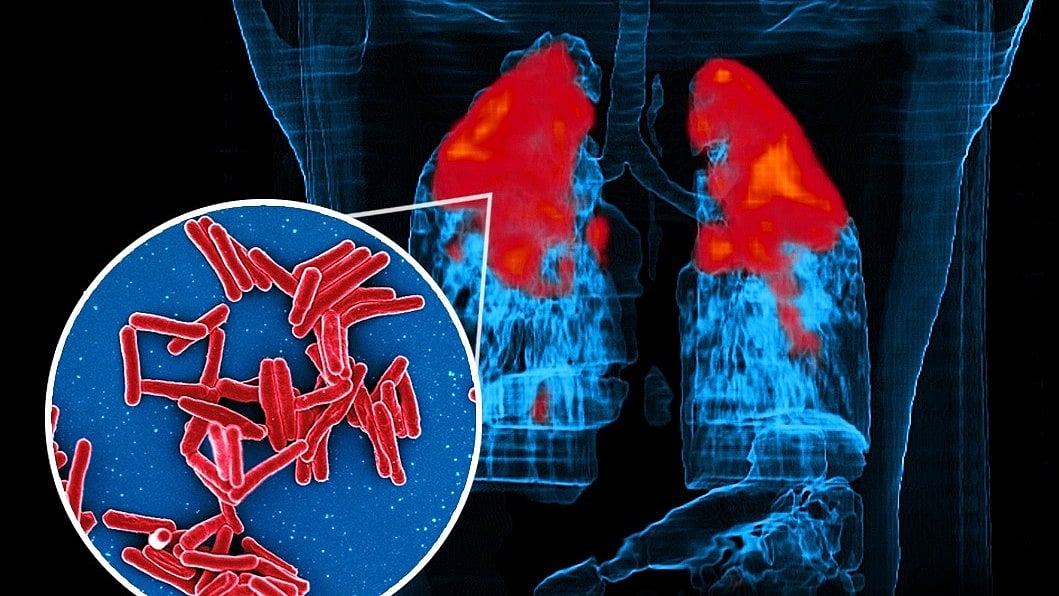

Tuberculosis remains one of the world’s most serious infectious diseases. In 2023, an estimated 10.8 million people were infected and 1.25 million died. India carries the highest burden, with over 2.6 million cases in 2024. A major reason TB treatment takes months is that the bacteria can switch into a dormant state where they become inactive but survive for long periods.